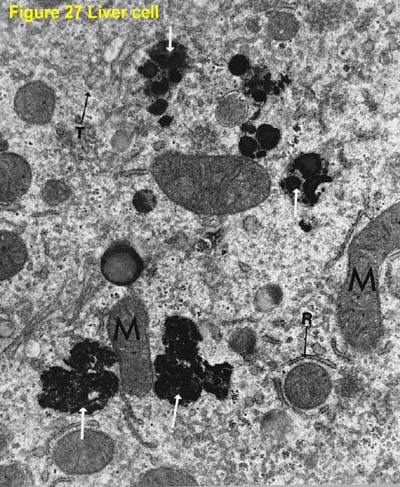

Figure 27 Liver cell.

Note prominent secondary lysosomes (white arrows) and mitochondria (M). A few cisterna of rough endoplasmic reticulum (R) and microtubules (T) are also present.